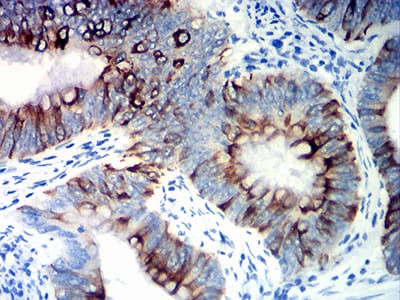

分类: 科研抗体货号: 31807别名: K20; CD20; CK20; CK-20; KRT21应用: IHC反应种属: Human